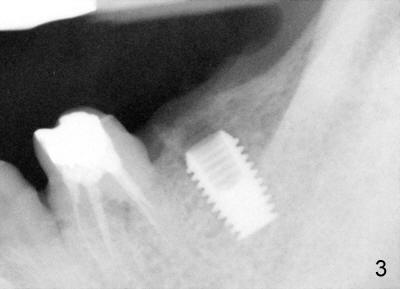

Fifty-four year old lady had had discomfort with a cantilever bridge (FPD) that restored #18 (Fig.1) and agreed to have FPD removed (Fig.2) and place implant (Fig.3: 5x8) 22 months ago. The lingual plateau of the implant was exposed due to plate perforation (Fig.4: <). At implant placement, #19 was found to have recurrent apical periodontitis. This tooth had root canal retreatment (Fig.5: 19), build-up (Fig.6: B) and crown (Fig.7: C).